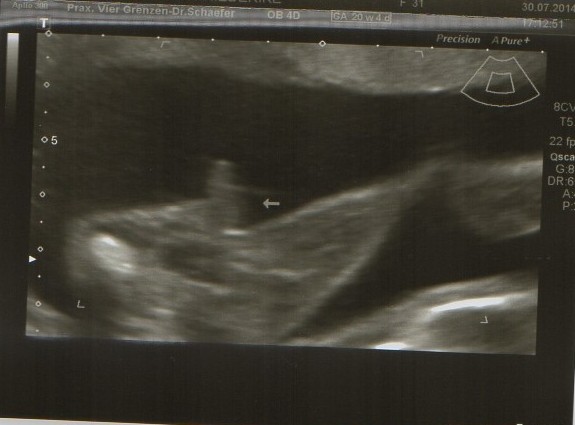

Heute gab es ein Fotoshooting der besonderen Art beim Opa auf Arbeit. Sein Kollege, der stellvertretende Chefarzt der Kinderklinik und gleichzeitig Guru des Ultraschalls, hatte sich bereit erklärt den werdenden Eltern noch ein paar aktuelle Fotos zu machen. Leider gab es kein 3D, aber dafür ein paar süße Fotos und vor allem Videos unseres Sohnemannes, der sich die ganze Zeit über ruhig verhielt und sich der Kamera, äh dem Schallkopf stellte.